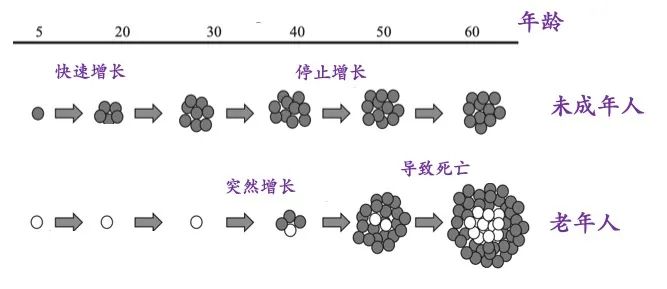

77岁的仇老伯(化名),1个多月前在检查发现PSA升高(tPSA:8.423ng/ml,f/tPSA比率:8.4),进行前列腺穿刺活检后,病理确诊为前列腺癌(腺泡腺癌,Gleason评分3+4=7分,pT2aN0M0),有进一步行前列腺癌根治性切除手术的指征,但目前前列腺癌根治性手术存在一定的并发症可能,如勃起功能障碍、尿控差、切缘阳性等问题,可能影响后续的生活质量,并给患者带来心理负担。

仇老伯听闻我院成兵主任是泌尿肿瘤方面的专家,再三思考和权衡之后找到了他。成兵主任结合仇老伯的具体情况,为了尽可能提高他的前列腺癌治疗效果,同时满足他对于“微创、不影响身体功能”的就医要求,决定为仇老伯进行多模态AI影像融合下前列腺癌“不可逆电穿孔”消融术,为此,特邀泌尿外科马利民教授共同为仇老伯手术。

马利民、成兵团队术前依据患者的前列腺MR结果精准定位病灶,围绕病灶勾画出布针靶区,结合了超声的实时性和MR的高对比度的优势,术中根据术前已画出的病灶范围精心实施布针方案,大大减少了手术时长。

布针结束后依次在各组不可逆电穿孔针之间通电,第一个循环电场设置为1500v/cm,脉冲数为150个,第二个循环电场设置为100v/cm,脉冲数为100个。经过35分钟不可逆电穿孔消融,华东地区首例多模态AI影像融合下前列腺癌“不可逆电穿孔”消融术顺利结束。